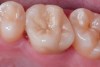

Fig 9. Preoperative view (Fig 9), preparation with composite block-out restoration (Fig 10), and final cementation of CL-IIb material (Fig 11) (final ceramic contour and stain by Steve Lee, CDT, MDC).

Figure 9

Fig 10. Preoperative view (Fig 9), preparation with composite block-out restoration (Fig 10), and final cementation of CL-IIb material (Fig 11) (final ceramic contour and stain by Steve Lee, CDT, MDC).

Figure 10

Fig 11. Preoperative view (Fig 9), preparation with composite block-out restoration (Fig 10), and final cementation of CL-IIb material (Fig 11) (final ceramic contour and stain by Steve Lee, CDT, MDC).

Figure 11